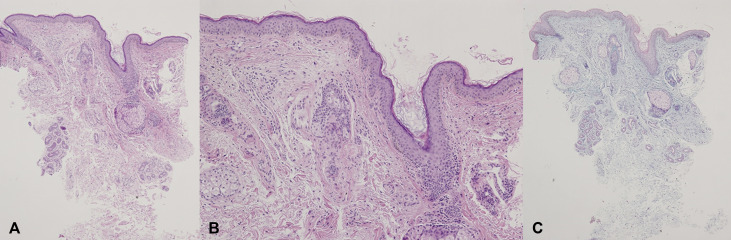

病例三:患者为59岁韩国男性,伴有3个月眼睑及面部持续肿胀的病史(图2),被诊断为过敏性接触性皮炎,使用泼尼松龙

和抗组胺药治疗1个月,未出现好转。1个月后,对左上眼睑进行皮肤活检,组织病理学分析显示胶原束间有无定形物质沉积,真皮上部伴有血管周淋巴细胞浸润(图3,A和B)。

Alcian蓝(图3,C)和促甲状腺激素染色结果均为阳性。根据临床和组织学表现,考虑甲状腺眼病。进行甲状腺功能和自身抗体检测,实验室检查未发现甲状腺自身抗体,甲状腺功能检查结果正常。患者被诊断为甲状腺功能正常眼病。

图2 双侧上眼睑存在局部界限不清的肿胀,左上眼睑肿胀较明显

图3 组织病理学检测结果